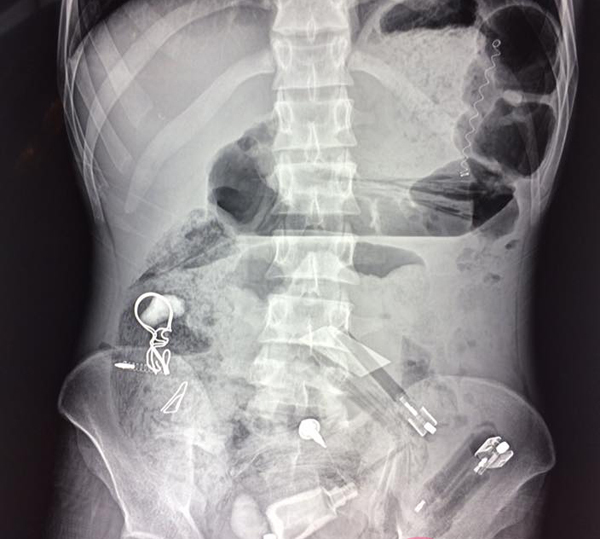

Kết quả chụp X-quang cho thấy, trong dạ dày bệnh nhân có rất nhiều dị vật với các hình dạng khác nhau, đâm thủng cả ruột.

| Ảnh chụp X-quang phát hiện nhiều dị vật trong bụng bệnh nhân |

| Các dị vật được lấy ra khỏi dạ dày bệnh nhân |

Ngay lập tức, bệnh nhân được mổ cấp cứu. Sau 3 tiếng, các bác sĩ lấy ra được hàng loạt dị vật từ lá cây, bút bi, thìa nhựa, túi nilon, vỏ kẹo, vỏ thuốc, lò xo...

Theo các bác sĩ, đây là trường hợp cực kỳ hy hữu, chưa từng gặp.